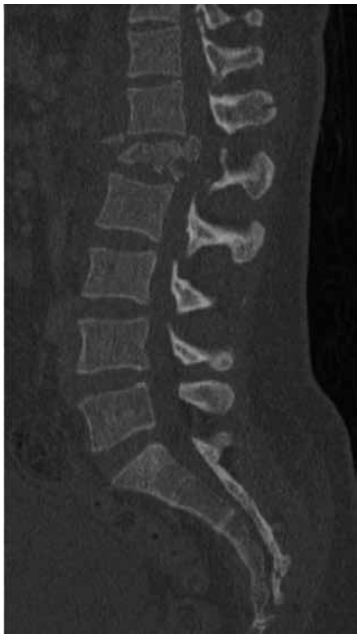

Paciente de 87 anos de idade relata dor na região lombar, em queimação, que irradia para membro inferior direito, associada a formigamento. A dor surgiu de forma súbita após o paciente desequilibrar-se e sofrer uma queda com impacto na região glútea. Desde então, a dor vem de forma contínua, sem fatores de melhora ou piora. Foi realizada uma ressonância magnética da coluna:

(Arquivo pessoal; imagem usada com autorização)